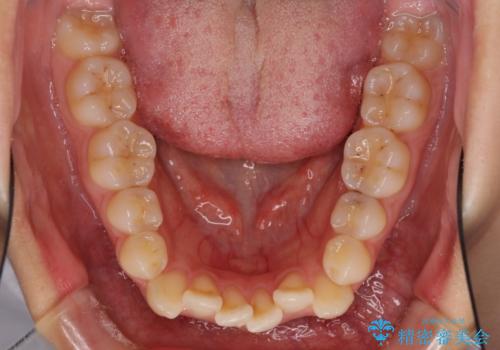

- 上の八重歯を気にして来院された患者様です。

受け口傾向にあるため、上顎前歯の叢生解消とともに下顎前歯を後方へ移動させることを目的とし、上下左右の第一小臼歯4歯を抜歯することとしました。